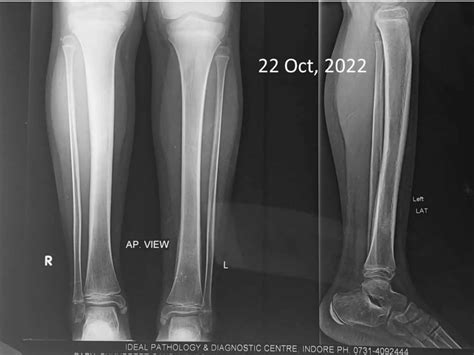

Diagnostic Approach and Imaging

Diagnosing Chronic Multifocal Osteomyelitis is a process of exclusion. Because there is no single laboratory blood test that confirms the diagnosis, physicians rely on a combination of clinical findings, imaging, and, in some cases, a bone biopsy to rule out other more serious conditions like malignancy or bacterial osteomyelitis.

X-rays Useful for evaluating bone damage, though often normal in the early stages.

💡 Note: A whole-body MRI is highly recommended by specialists to identify asymptomatic lesions that might otherwise go undetected.